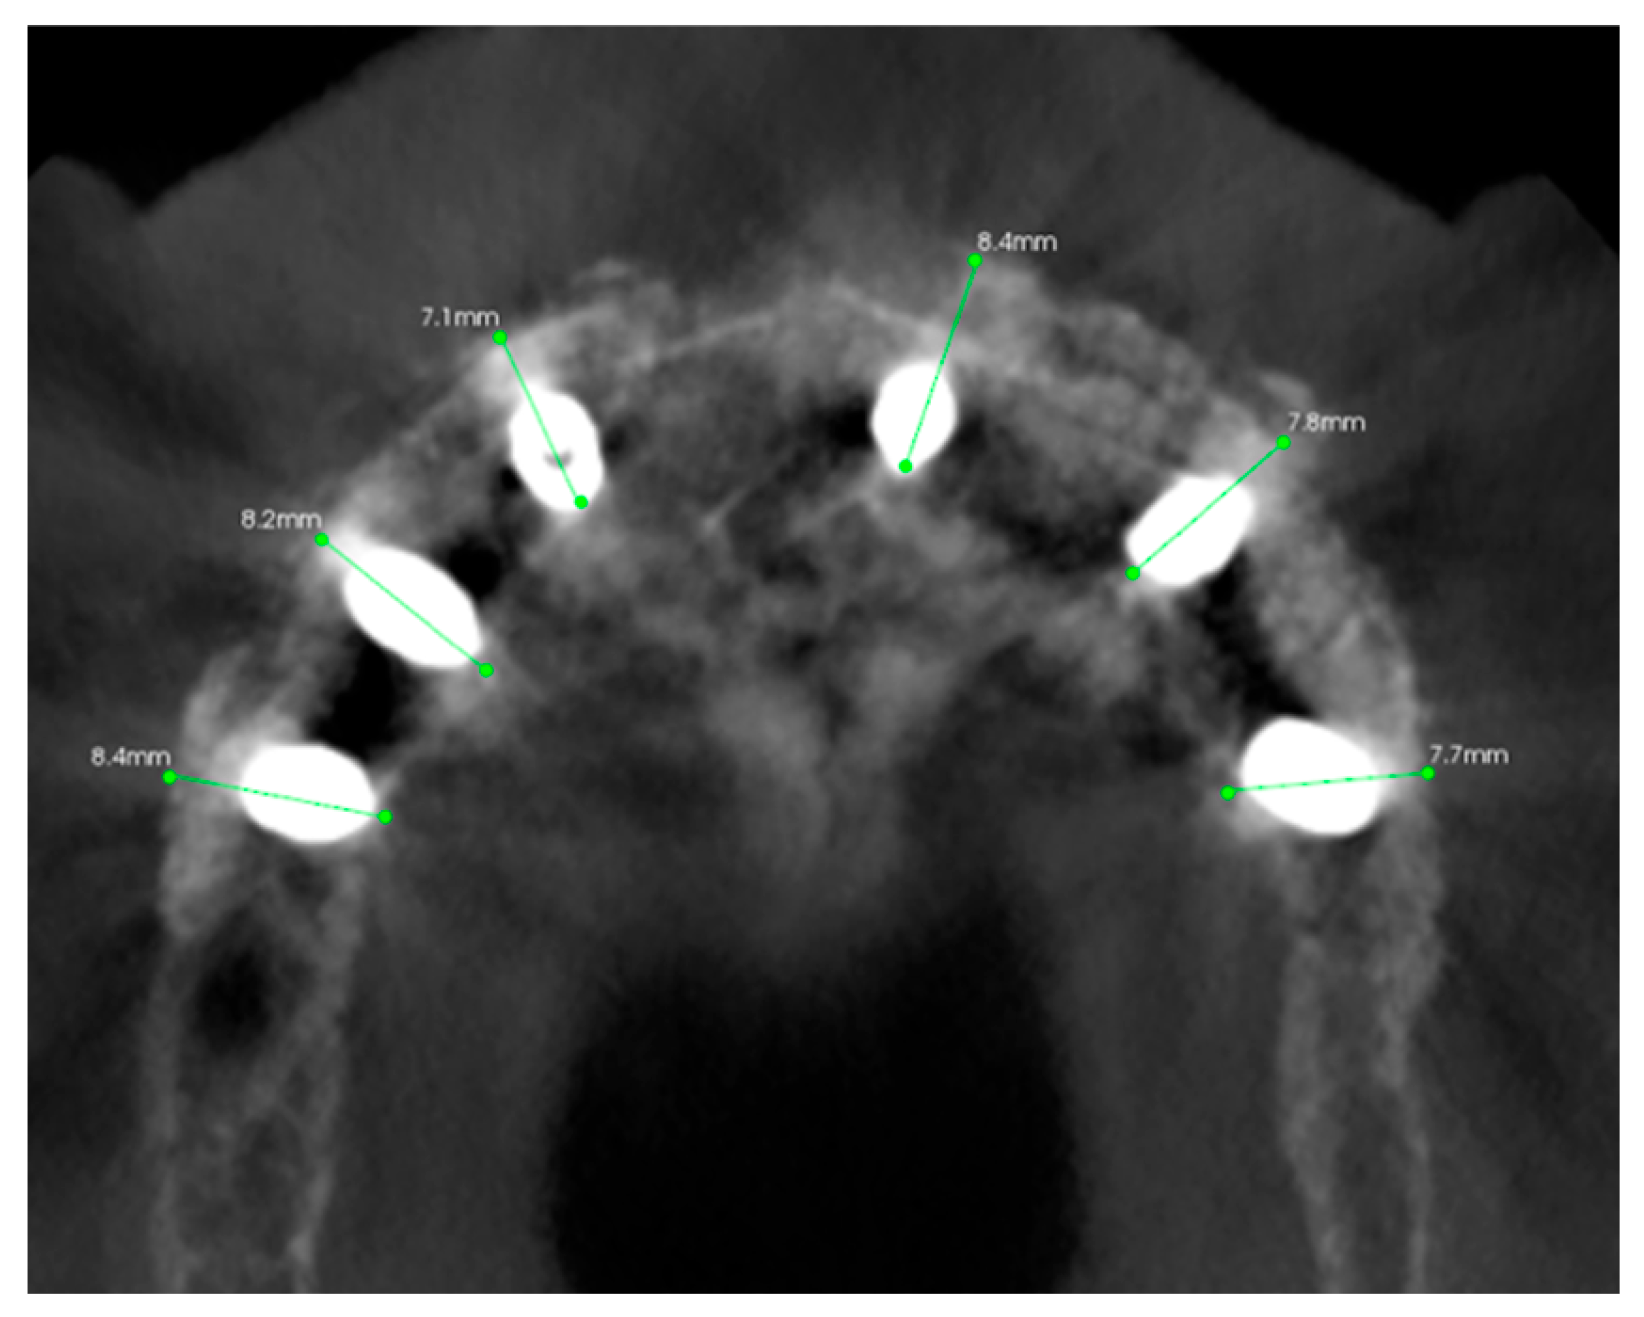

3.3. Hard Tissues Gain